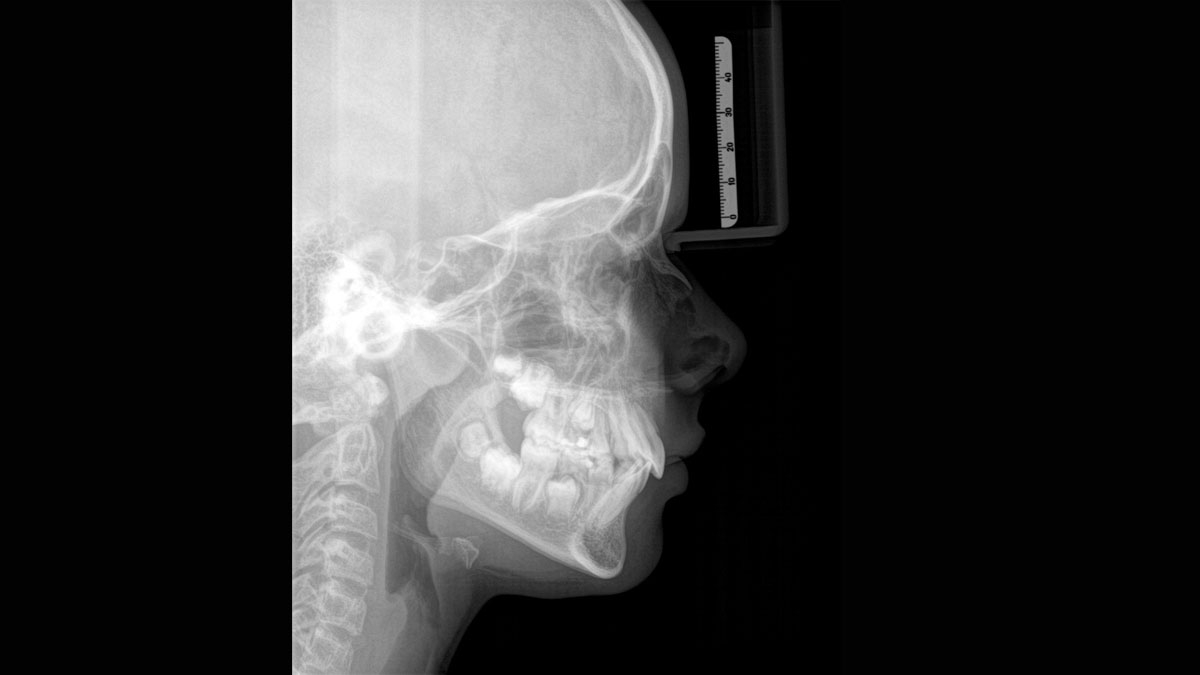

При помощи такого оборудования специалист сможет успешно решить широкий спектр диагностических и лечебных задач. Качественное изображение, достоверность при разноуровневой резкости (технология Sharp Layer), гибкий объём, 30 доступных вариантов цвета. Цефалометрическая визуализация позволяет получать боковые или симметричные снимки, а также определить положение при смещении зуба. Работая при разрешении до 80 мкм в режиме низкой дозы и HD, вы получаете качественные изображения выбранного формата, заботясь о комфорте и безопасности пациента.

Диагностика последнего поколения, идеально решающая задачи рентгеновского обследования независимо от размеров клиники. Поля изображения зависят от определенной клинической картины, поэтому специалистам так удобно работать с ORTHOPHOS SL 3D. Данная установка делает объёмные картинки для одиночной реставрации в 3D качестве полностью всей челюсти такого размера, которого требуется.

Датчик DCS служит для выставления резкости снимков, причём его технологические особенности можно считать революционными для современного рынка стоматологического оборудования.

Конструктивные особенности датчика DCS заключаются в превращении рентгеновского излучения в электрическую энергию. Обычная для таких случаев промежуточная стадия светового луча отсутствует. Другими словами, значительно снизив потери сигнала, производитель максимально улучшил чёткость.

С технологией SL можно за один сеанс получить огромное количество снимков. Те из них, где фокусировка наиболее чёткая, автоматически соединяются. В итоге одна процедура — снимки челюсти полностью в самом лучшем качестве. Даже нестандартные случаи не станут помехой в обследовании. К примеру, при ретинированных зубах уже после того, как снимок сделан, нужную область можно выделить подробнее, и в ещё одном рентгене необходимость отпадает.